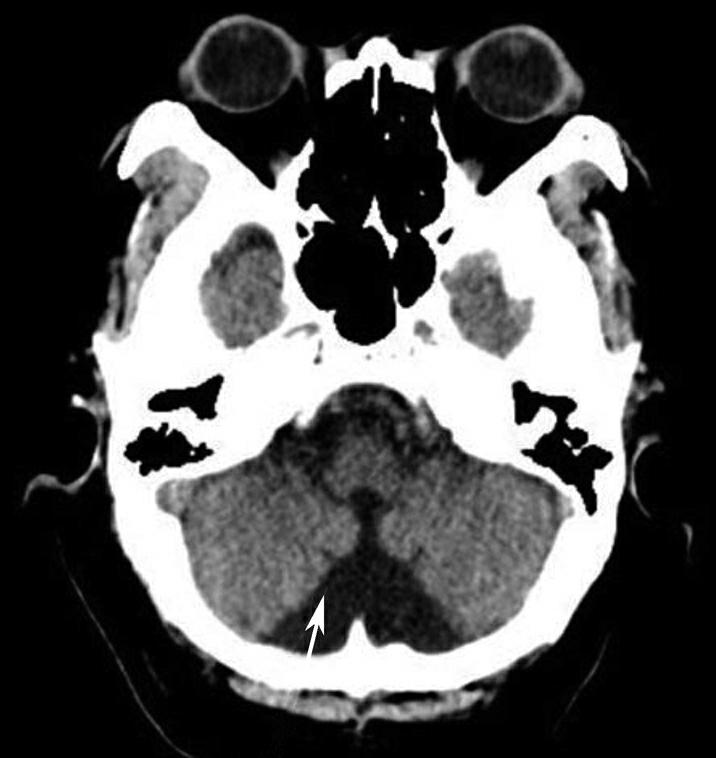

Alberta卒中项目早期CT评分(Alberta stroke program early CT score,ASPECTS)是一种评价急性缺血性卒中患者大脑中动脉供血区早期缺血性改变的简单、可靠、系统化的方法,是常用的脑卒中评定量表之一,可对缺血性病变快速进行半定量评价,有助于判定溶栓效果和远期预后。该评分主要基于CT平扫,具体分区如下(图1-2-76)所示,即选取大脑中动脉供血区2个层面。分区后共10个区域,每个区域记1分。评分时任何区域只要有低密度灶,则扣除该区域得分。正常脑ASPECTS评分为满分(10分),若MCA供血区广泛梗死累及全部区域时,则ASPECTS评分为0分。

图1-2-76 ASPECTS评分脑组织分区

A.在基底节层面(即丘脑和纹状体平面),分为各级分支M 1 、M 2 、M 3 、岛叶(缩写I)、豆状核(缩写L)、尾状核(缩写C)和内囊(缩写IC)后肢等7个区域;B.在基底节以上层面(基底节层面上2cm),包括M 4 、M 5 和M 6 。